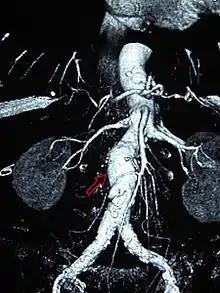

| CT reconstruction image of an abdominal aortic aneurysm (white arrows) | |